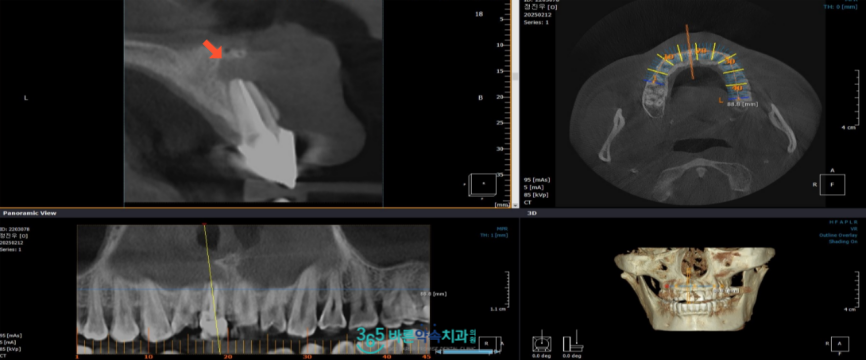

망원동치과 356바른약속에서는

더욱더 정밀한 검사를 위해

3D CT 촬영을 통해 염증의 위치와

크기 등을 정확하게 확인하는

과정을 거쳤는데요.

면밀하게 검사하고 진단한 결과

해당 치아를 발치하지 않고

세균인 원인인 치근단 부위를 절제하여

자연치아를 좀 더 사용할 수 있도록

치근단 절제술을 진행하기로

치료 계획을 수립하였습니다.

치근단 절제술 후 1주일 정도 뒤

실밥을 제거해 드렸으며

잇몸뼈 회복 상태를 확인하기 위해

파노라마와 3D CT를 촬영해 보았더니

염증이 깨끗하게 제거가 되었고

뿌리끝이 단단히 메워져 있는 것을

확인할 수 있었습니다.